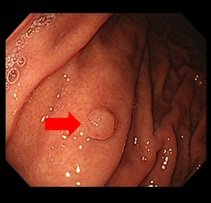

- 胃内視鏡検査

| 胃、食道、十二指腸などの病変の有無を調べる検査です。 本検査は主に食道炎などの炎症の有無、食道癌や胃癌などの癌の診断、吐血などの原因部位の特定などを目的としています。 病変の状態によってはその場で治療を行うこともあります。 また、本院では、経鼻内視鏡を用いた検査も行っているので、従来の経口型では不快感がある方でも、より楽に検査を受けることが可能です。 |

|

| 胃ポリープ |